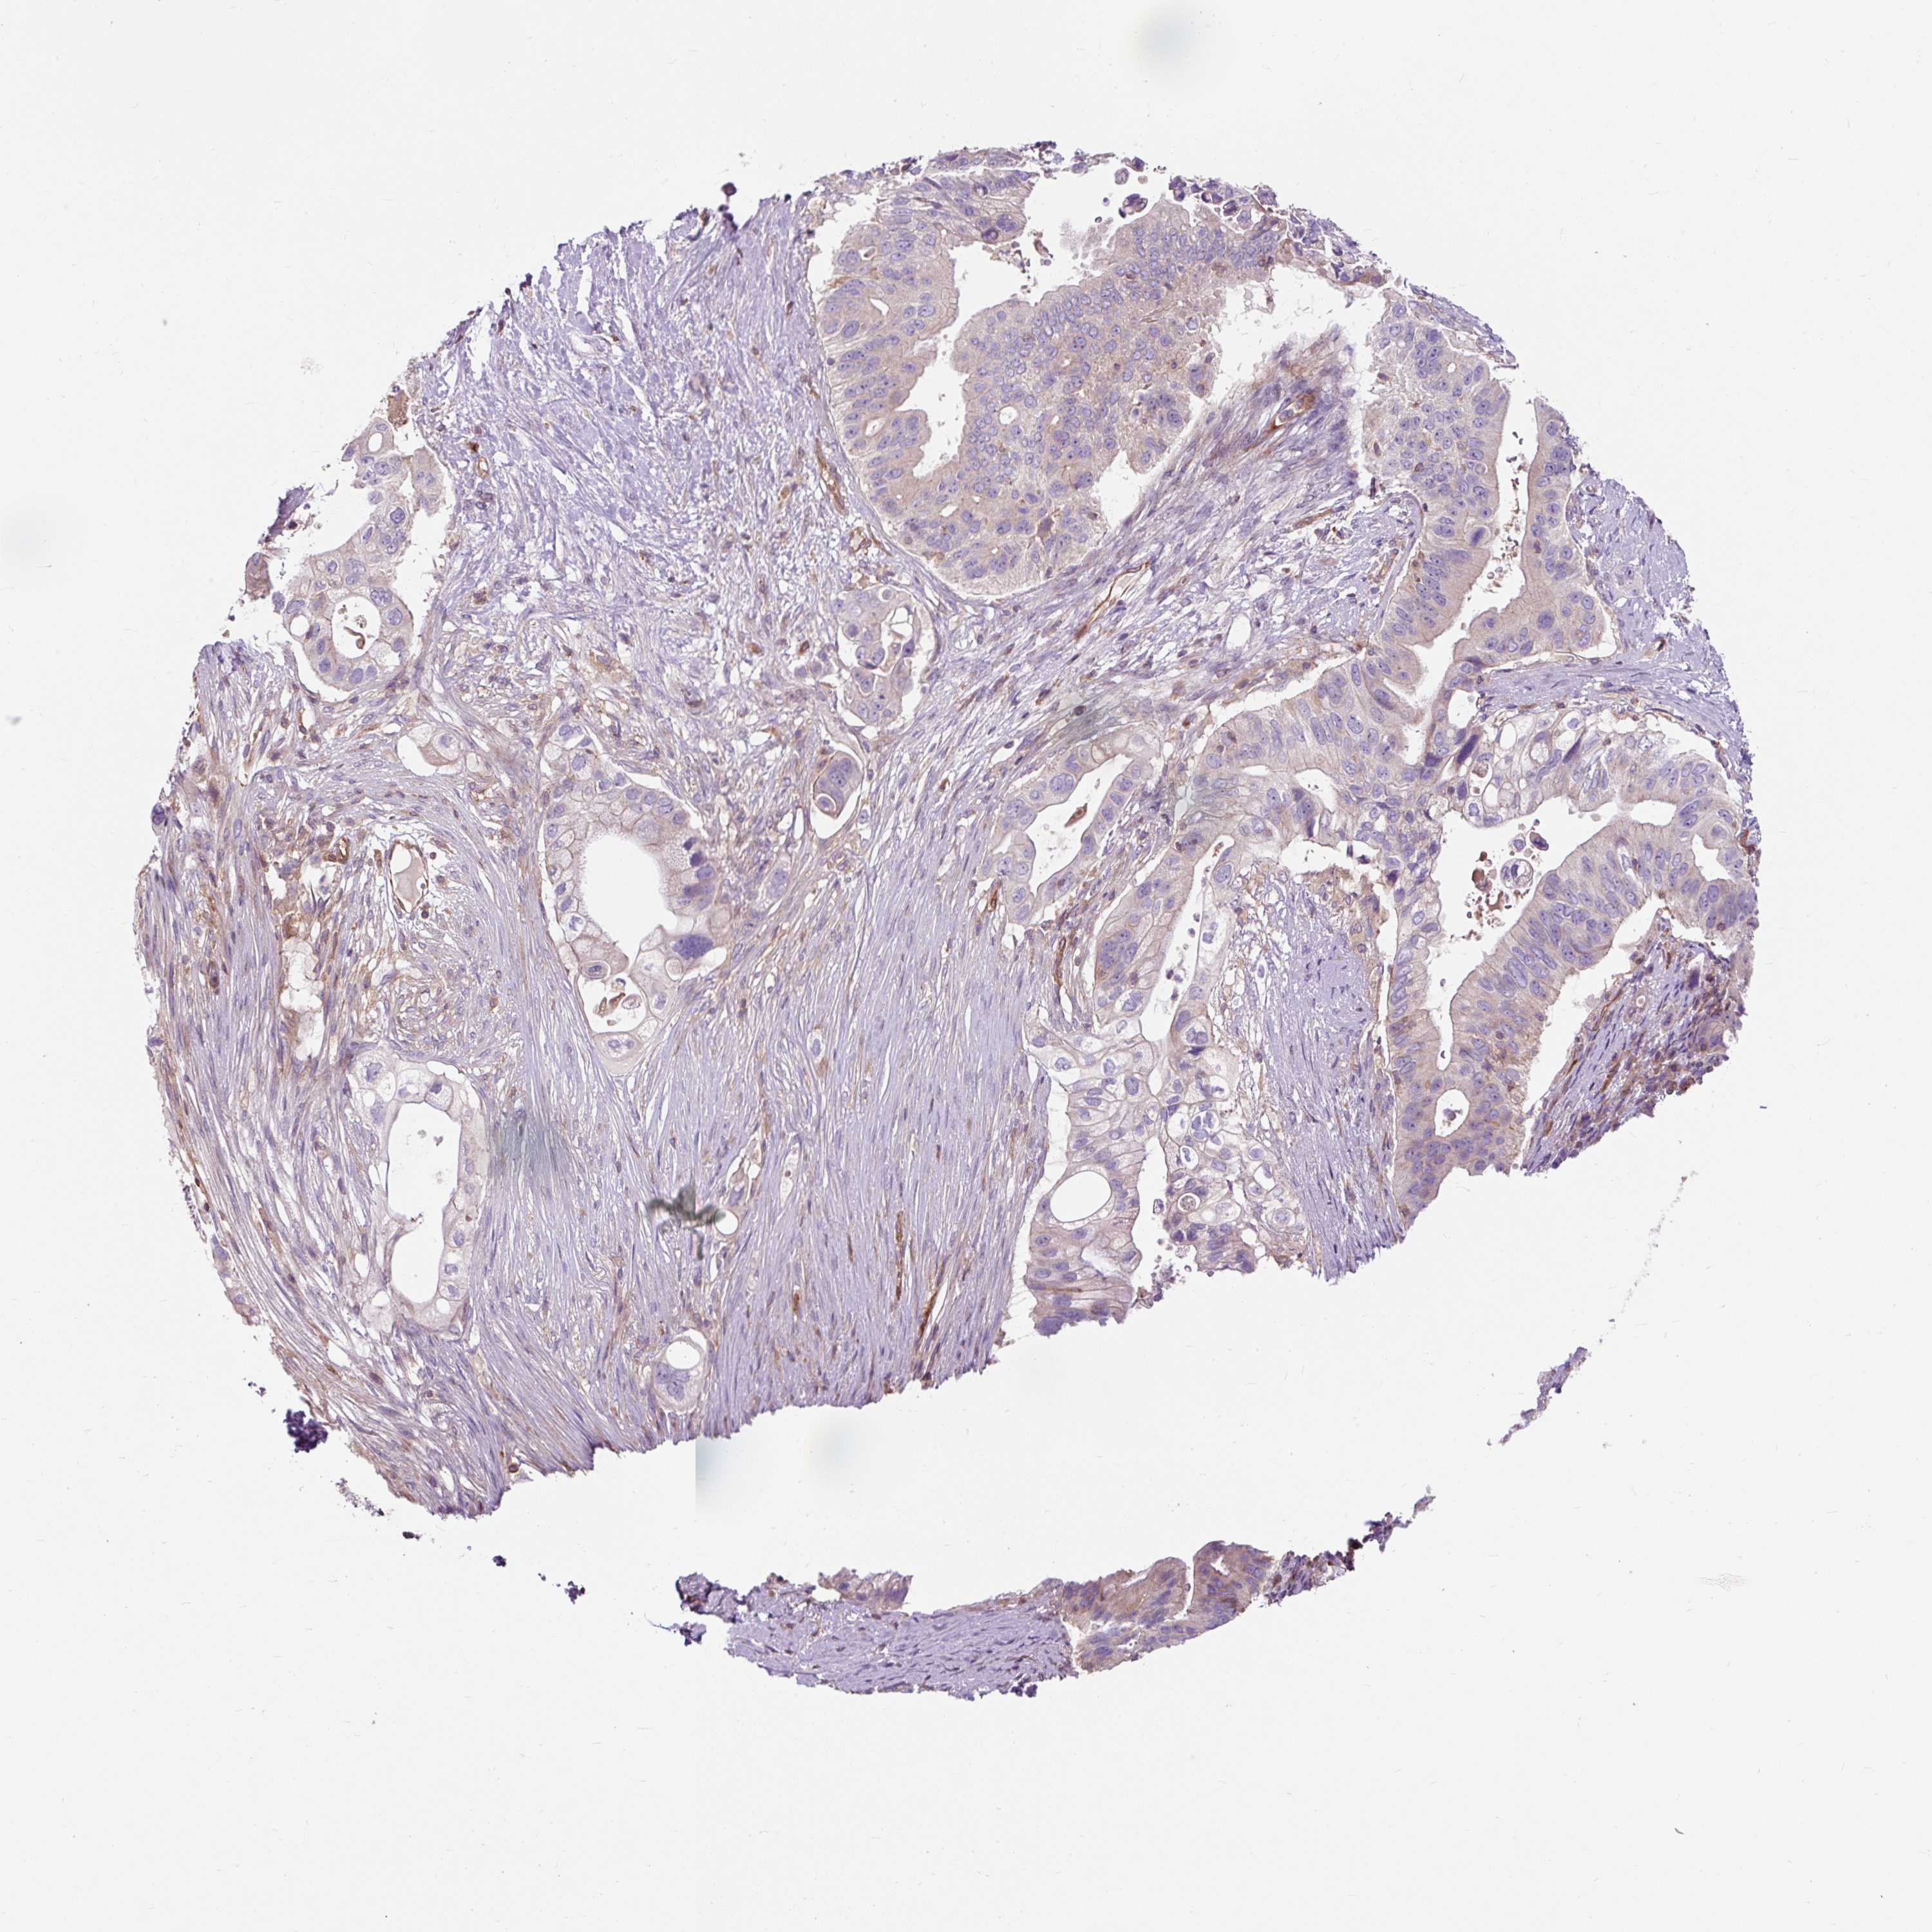

PANCREATIC CANCER - Protein expressioni

A mouse-over function shows sample information and annotation data. Click on an image to view it in a full screen mode. Samples can be filtered based on level of antibody staining by selecting one or several of the following categories: high, medium, low and not detected. The assay and annotation is described here.

Note that samples used for immunohistochemistry by the Human Protein Atlas do not correspond to samples in the TCGA dataset.

Antibody stainingi

Antibody staining in the annotated cell types in the current human tissue is reported as not detected, low, medium, or high, based on conventional immunohistochemistry profiling in selected tissues. This score is based on the combination of the staining intensity and fraction of stained cells.

Each image is clickable and will lead to virtual microscopy that enables deeper exploration of all samples and also displays staining intensity scores, fraction scores and subcellular localization as well as patient and tissue information for each sample.

Antibody HPA008755

Antibody HPA035823

Adenocarcinoma, NOS

Adenocarcinoma, metastatic, NOS